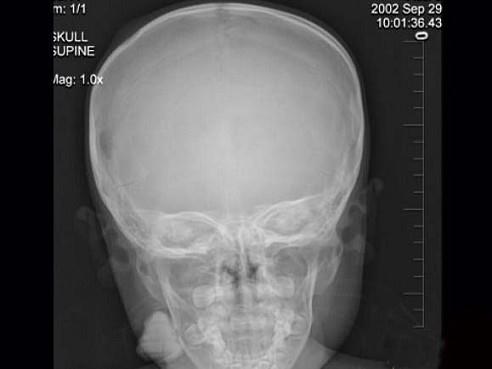

问题 3岁男孩,发热伴头顶部局限性疼痛1周,头颅正侧位示右侧额顶部局限性骨皮质缺损,最可能的诊断是 ( )

选项 A、局限性骨皮质缺损 B、先天性颅骨缺损 C、嗜酸性肉芽肿 D、蛛网膜颗粒压迹

答案 C